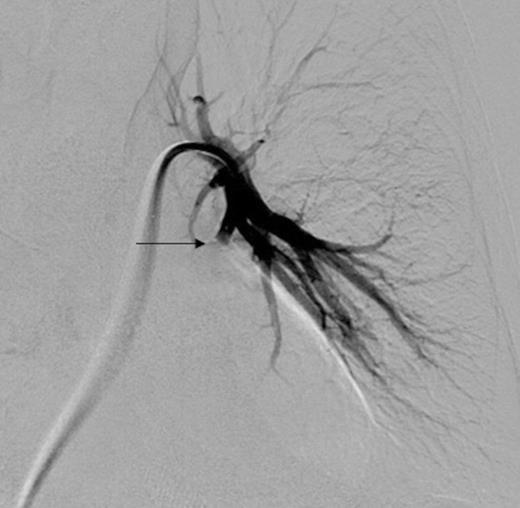

Left pulmonary artery digital subtraction angiography image demonstrating filling of left lower lobe aneurysm (arrow)

Three days later he presented with significant haemoptysis. A CT pulmonary angiogram (CTPA) demonstrated an increase in size of the PAA from 14mm to 28mm (Figure 1) diameter. A radiology opinion was sought and the patient transferred to the angio-suite for intervention.

Digital subtraction angiography post deployment of the AVP 4 device in the PA branch feeding the aneurysm (arrow). No residual or collateral filling seen